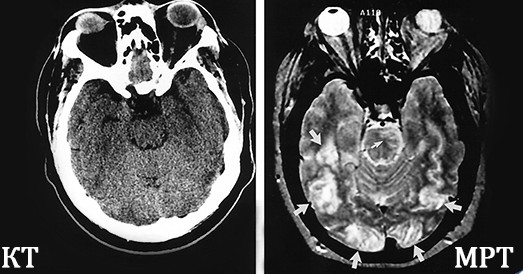

Обследование головного мозга также определяет, какая разница между КаТэ и МРТ. С помощью магнитного томографа определяют ишемический инсульт, новообразования, аномалии развития. А компьютерный томограф более эффективен при остром нарушении мозгового кровообращения по геморрагическому типу и свежих черепно-мозговых травмах. При патологиях сосудов МРТ имеет важное преимущество - для такого исследования не обязательно вводить контраст, в отличие от КТ.

Если посмотреть фото, то отличие МРТ от КТ будет особенно бросаться в глаза при обследовании позвоночника. При компьютерной томографии лучше видны все отростки и изменения позвоночного столба. При магнитно-резонансном методе обследования будут визуализироваться грыжевые выпячивания и другие патологии.